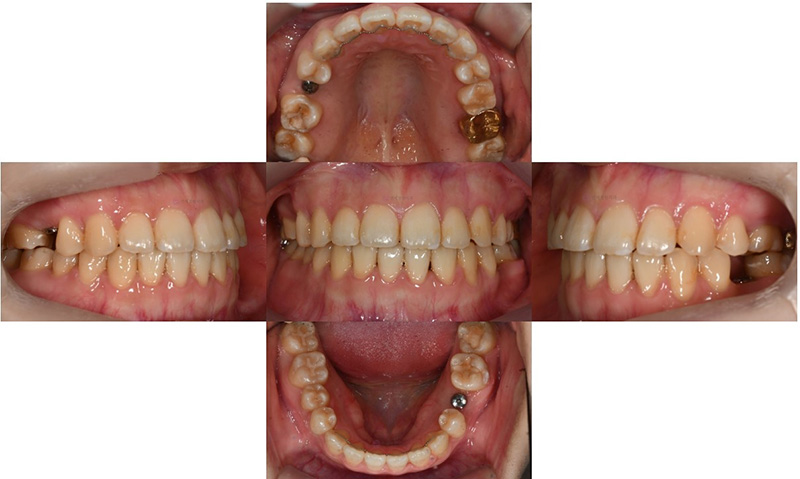

교정치료 마무리 후의 모습으로, 오른쪽 아래 작은 어금니는 제위치에 잘 위치하고 있으며, 나머지 두 군데 작은 어금니가 없는 부위에는 임플란트를 식립하였습니다.